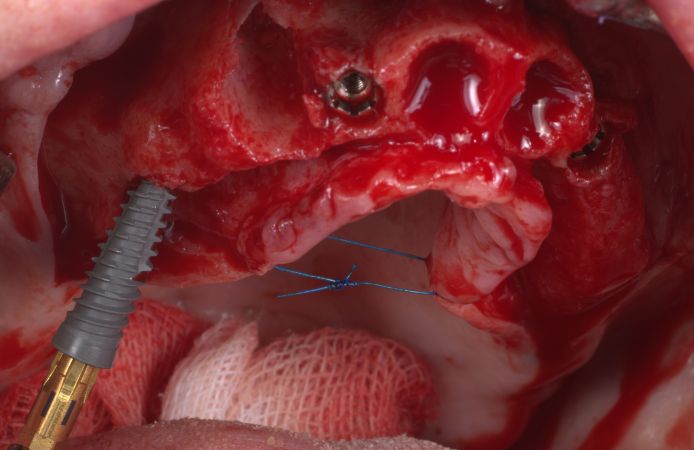

Figure 6.

The two posterior implants (4.5 x 15 mm) were tilted to maximize the distance between the implants, to avoid the sinus, to maximize the contact with available bone, and to increase stability.